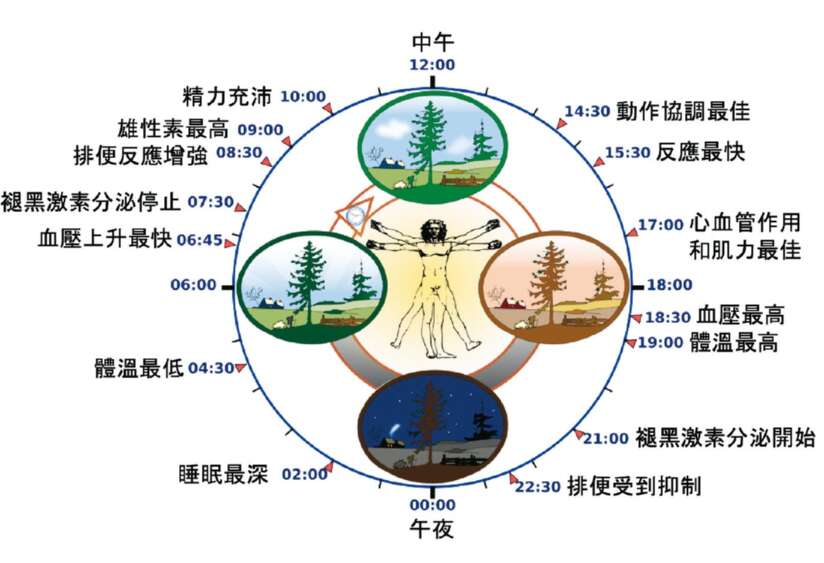

站在內分泌的角度,我通常會談兩大類荷爾蒙,一個是皮質醇,另一個是褪黑激素,對我們的睡眠最重要。透過右頁這張圖,我們可以看出它們兩個本身就有自己的日週期,而起伏的步調是不同的。

其中,交感神經系統是幫助我們面對生存的考驗,讓肌肉收縮,呼吸和心跳加快……隨著一天開始,我們要面對種種的事,身體的交感神經系統也就啟動了。交感神經的活化,讓我們加強每一個部位的機能,活力變高,代謝加快。同時,讓我們覺得自己是清醒的。清醒的程度,是在早上10點達到高峰,而反應速度則是在下午3點達到最佳表現。

褪黑激素可以說剛好和皮質醇作用的時間相反,是在太陽下山後,9點開始分泌,夜裡11〜12點到高峰,到天亮時,已經幾乎消失。其實,褪黑激素的水平和我們的體溫變化趨勢是剛好相反的。到了夜晚,褪黑激素上升,而核心體溫逐漸下降,身體的作用程序也開始慢了下來。也就是說,我們要入睡,無論內分泌和全身的生理與代謝程序,都要同步朝向睡眠的方向前進。

✔ 「日週期」反映的其實不只是睡眠,而是人體運作的週期。

✔ 內分泌、血壓、心血管的效率、各種生理反應,都讓我們配合著太陽的週期而起伏,準備我們面對一整天。

✔ 到了夜晚,褪黑激素開始上升,核心體溫慢慢下降,身體也就準備進入睡眠。